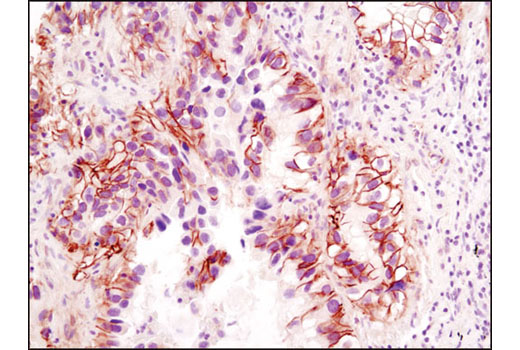

IHC-P (paraffin)

在对照肽(左图)或抗原特异性肽(右图)存在的情况下,使用 β-Catenin (D10A8) XP® Rabbit mAb 对石蜡包埋的小鼠结肠细胞进行免疫组织化学分析。